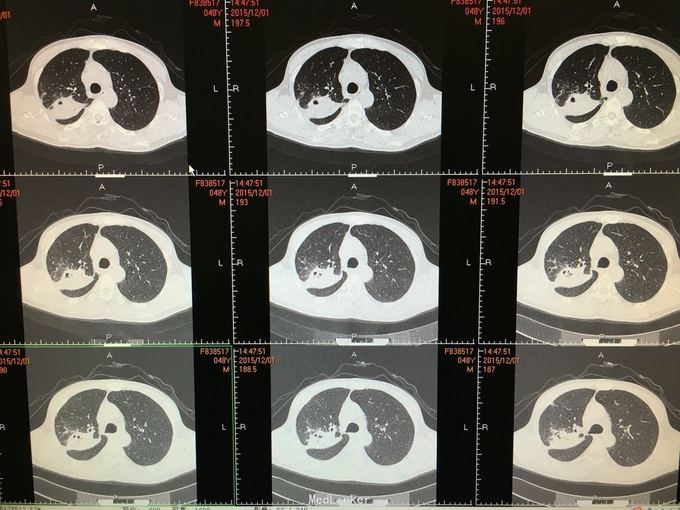

间断咳嗽咳痰5月余。患者缘于半年前确诊为骨髓增生异常综合征,并行造血干细胞移植术。术后出现发热,完善相关检查考虑为肺部真菌感染,给予抗感染治疗后体温正常,病情好转出院。出院后仍有间断咳嗽咳痰,咳黄色痰,无发热,自行口服伏立康唑200mg,2/日治疗,12月初复查CT提示双肺病灶较前进展,右肺中叶新增病灶。

根据症状体征及辅助检查,结合病史考虑真菌感染可能性大。进一步气管镜检查,结果如下。组织活检标本可见。病理回报提示真菌团,培养见曲霉菌生长。明确诊断后给予两性霉素B雾化吸入及伏立康唑静脉应用抗真菌治疗,同时给予环孢素口服。

造血干细胞移植后肺部感染常见,其中以曲霉、卡肺等多见,患者经气管镜检查已将真菌团块取出。术后给予监护,口服云南白药、垂体后叶素雾化止血等治疗,无明显出血,症状逐渐好转。复查CT也明显好转。